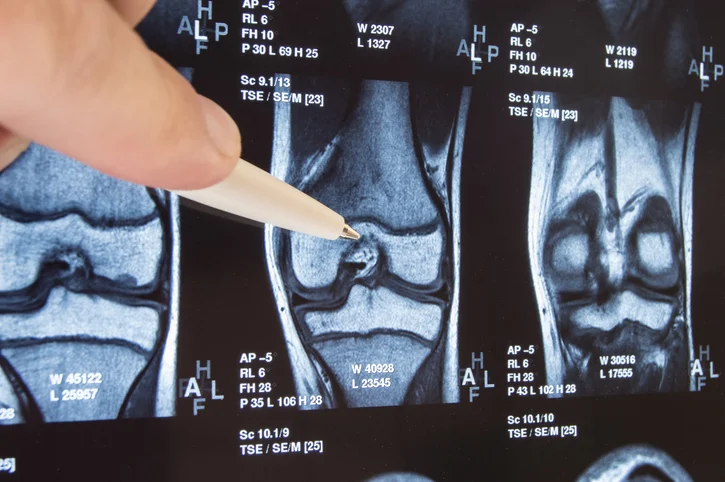

The golden rule of joint health is the more you move, the less stiffness you will have. Most of us take for granted and rarely consider the importance of good joint health. Our joints, located wherever the ends of two bones come together, are kept very busy each day. From waving our fingers goodbye, turning our head side to side, swirling our hips, or bending our knees to climb stairs, their job is priceless. But, if our joints become stiff, we pay the price by being unable to move with ease and comfort. All joints – vertebrae, elbows, wrists, knees, hips, ankles, fingers, and toes, allow movement of our skeleton keeping us mobile for many years.

But life happens – we grow older, we injure ourselves or we gain too much weight resulting in wear and tear on our joints, damaging them and possibly leading to arthritis. The best way to care for your joints is to keep them and the muscles, ligaments, and bones surrounding them, strong and stable. Here are 15 top tips on how to be good to your joints preserving their health: